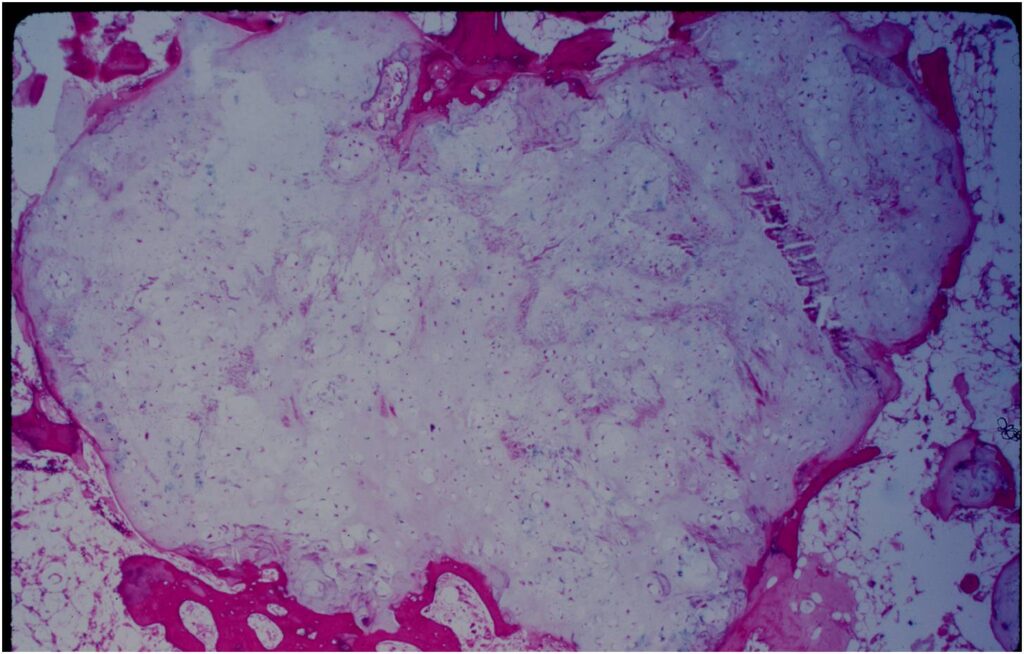

Gross Pathology

- Fragments of enchondroma after curettage are bluish white and glistening hyaline cartilage

- There may be yellow calcified foci

- Cartilage grows in a lobular manner and hence in a completely resected specimen there will be local lobules of mature cartilage

Microscopic Pathology

- Enchondromas are well defined lesions with cartilage arranged in lobules that are separated by fibrovascular septa

- Enchondral ossification may occur around periphery of lobules and when calcified appear as “Rings and Arcs” on X-rays